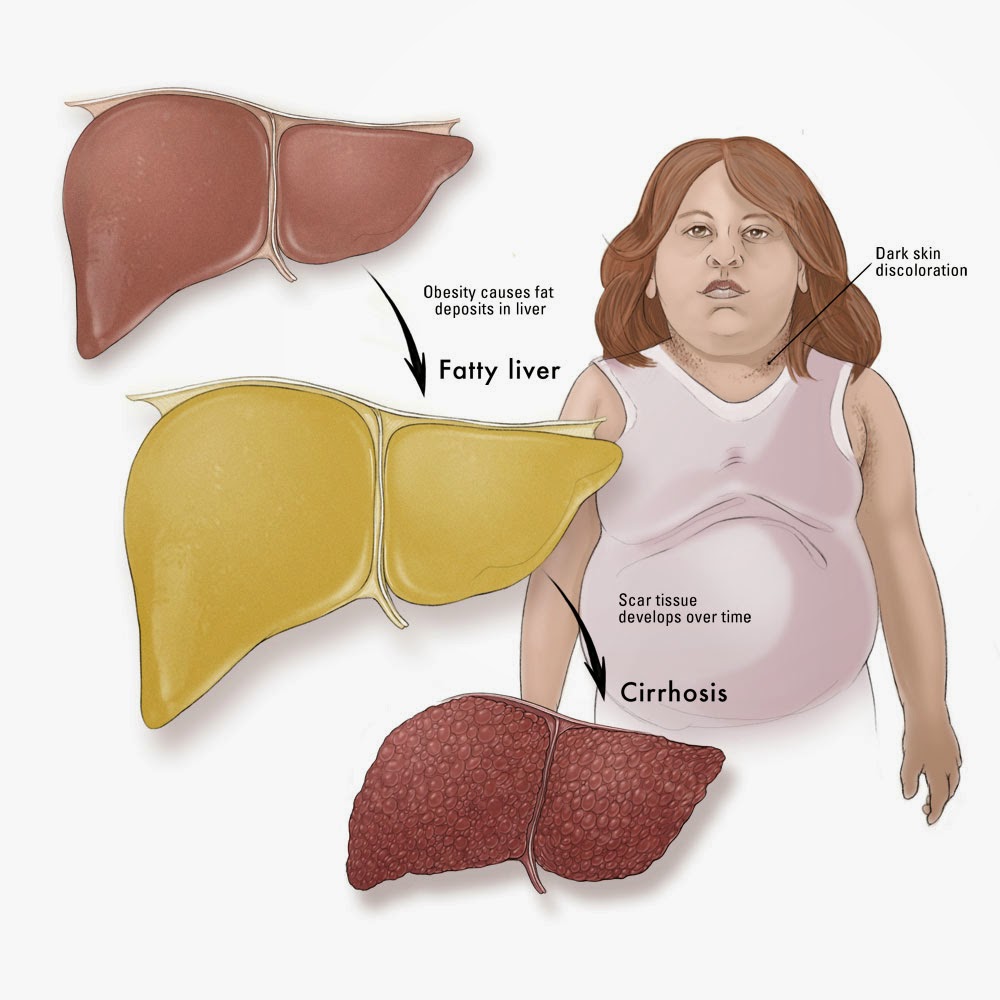

Stages of Liver Damage, Illustration – Stock Image – C027/6479 …

Stages of liver damage. Starting from a healthy liver (top left Stock …